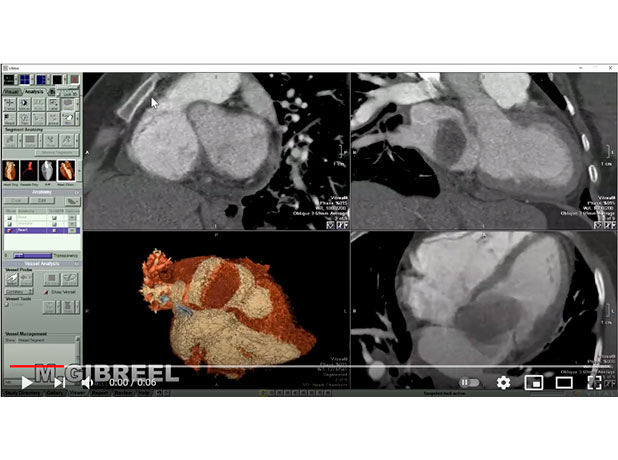

LA mass likely myxoma

Mohamed Gibreel , FEBR (Fellowship of Egyptian Board of Radiology ) Cardiac imaging consultant at Aswan heart center -Magdi Yacoub Foundation , Egypt